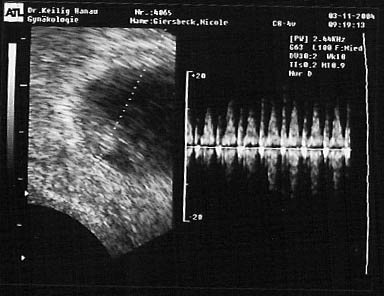

Meine Ultraschall-Bilder